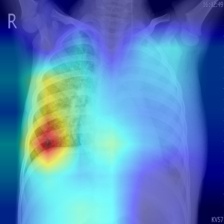

In order to compare the interpretability capacity of our model and the state-of-the-art models, we employ Grad-Cam [18] for heatmap visualizations on selected X-ray images. We show on a side-by-side basis how our model performs with superiority in Figures 4-7. We also observe that the addition of the attention block has a crucial role in focusing on the most relevant features in the images, which significantly assists the model during classification.